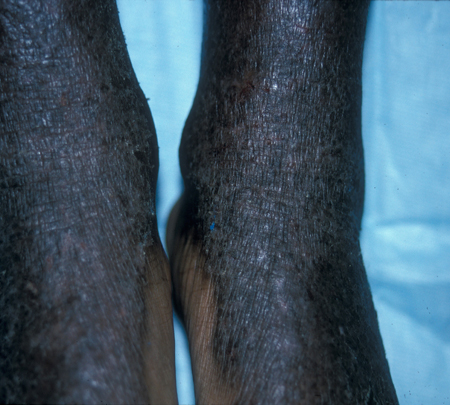

Sarcoma de Kaposi nos membros inferiores

Common skin diseases in HIV-infected patients in the antiretroviral era. IAS-USA 2007; usado com permissão